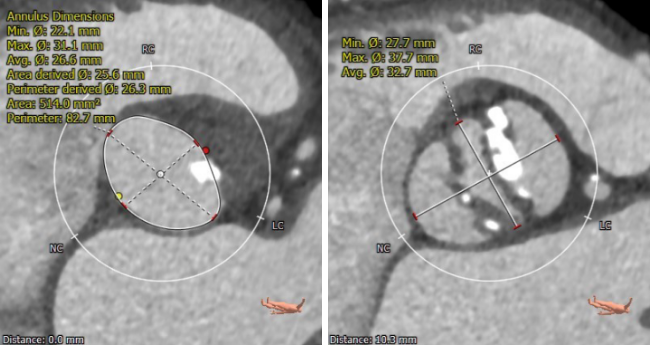

主动脉根部CTA

术前CT

Type0型二叶式主动脉瓣,重度钙化(HU850:968),钙化非对称性分布。瓣环周长82.7mm,周长径26.3mm,升主动脉平均直径44.3mm,窦管结合部平均直径36.9mm,左室流出道平均直径25.3mm,左冠开口15.6mm,右冠开口16.7mm。